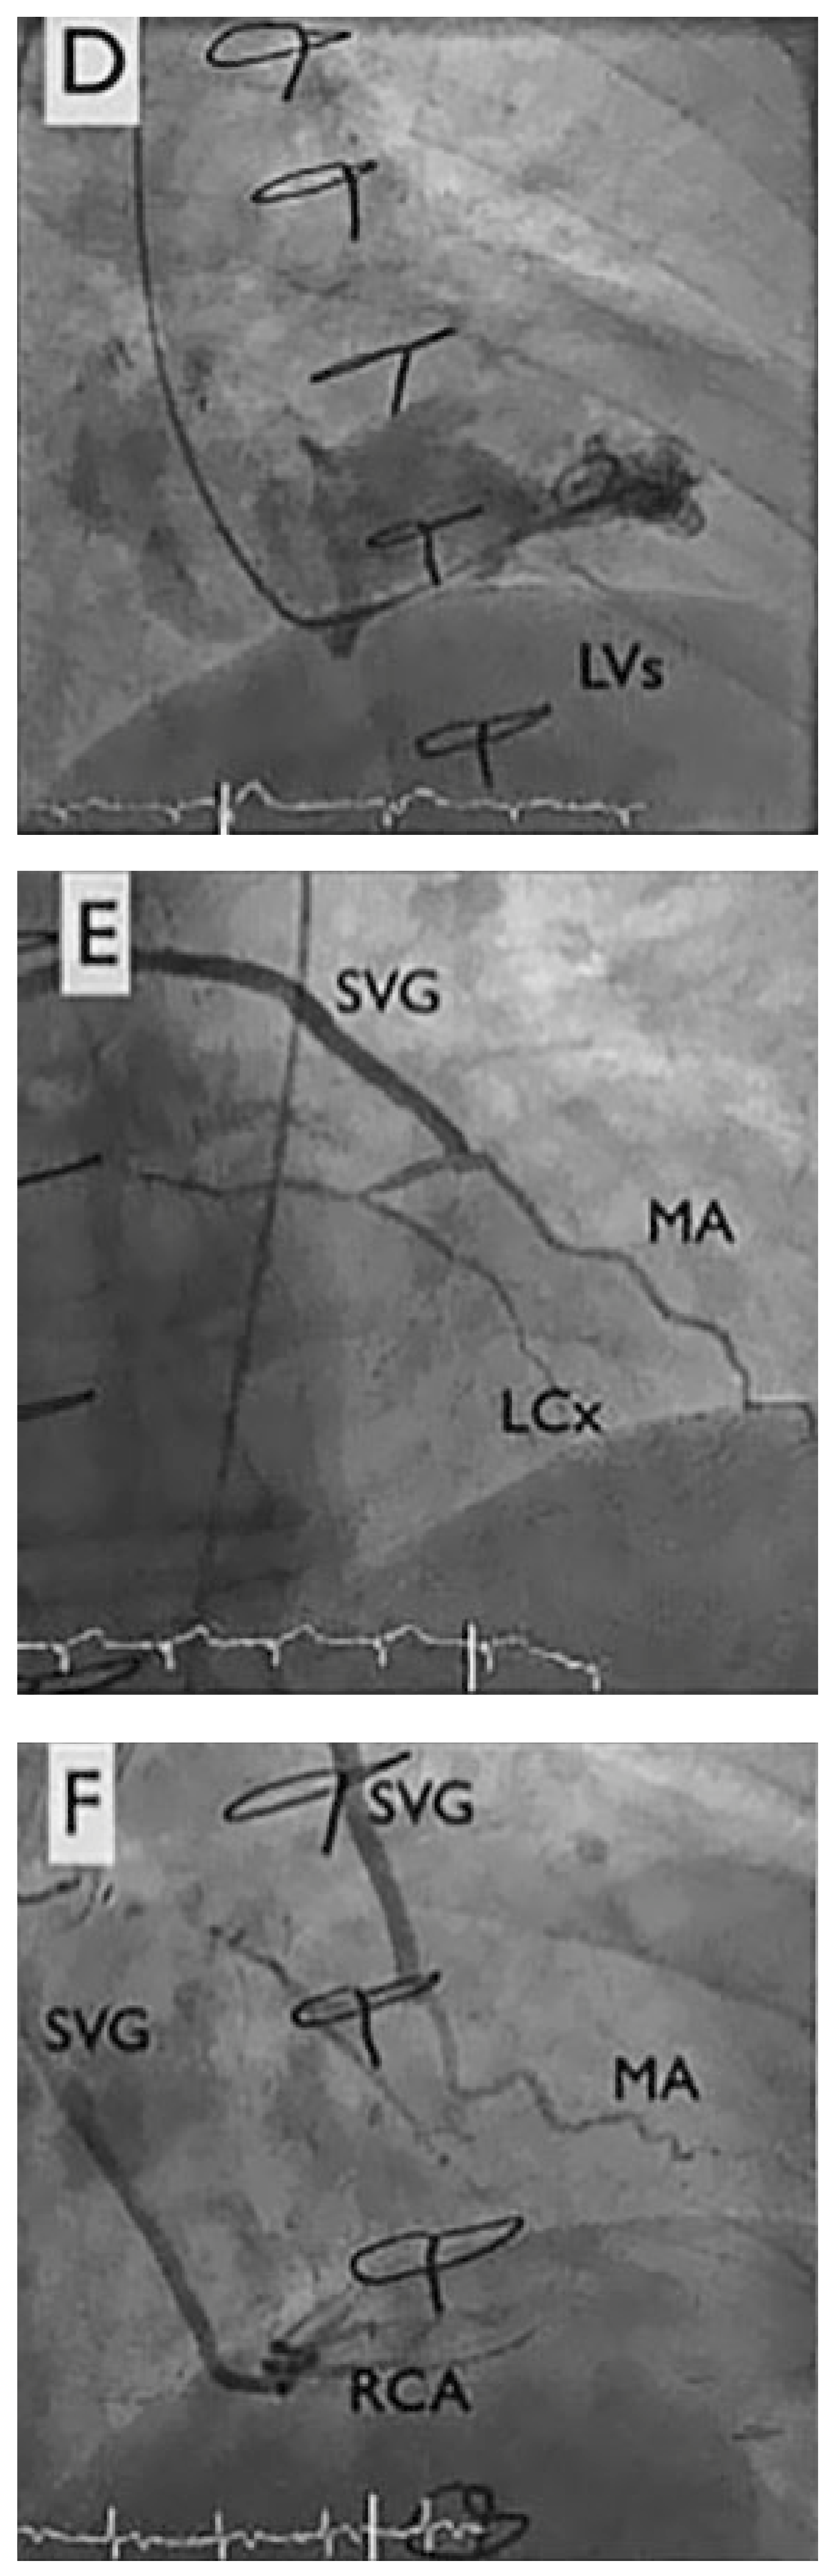

Coronary reduction (Figure 2A–F)

The right internal jugular vein was accessed under ultrasound guidance, followed by venography and measurement of the coronary sinus diameter (7 mm, central part). A 9 French delivery sheath was placed within the coronary sinus under fluoroscopic guidance. The reducer stent (Neovasc Inc., Richmond B.C., Canada) (Figure 2A), premounted on an hourglass shaped balloon catheter, was implanted downstream from the middle cardiac vein in the coronary sinus after a 5 atm. inflation of the balloon (Figure 2D). After de-inflation of the balloon and withdrawal of the balloon catheter, venography showed a 3-mm central restriction with good results (Figure 2F). The intervention was without complications such as occlusion, dissection of the coronary sinus, or bleeding at the jugular puncture site. The patient was discharged with 6 months of dual antiplatelet therapy (aspirin and clopidogrel). At 3-month follow-up, the patient was significantly improved, with complete disappearance of nocturnal events, significant improvement in exercise tolerance and improvement by two Canadian Cardiovascular Society (CCS) angina classes (IV to II).

Figure 2.

Coronary sinus reduction. Panel A by courtesy of Neovasc Inc., Richmond B.C., Canada. CS: coronary sinus, SVC: superior vena cava.